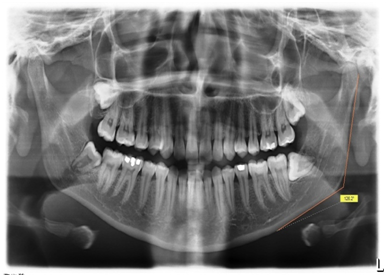

2. Gonial Index (GI): It was measured as the mandibular cortical width on the bisectrix of the angle between the two tangent lines forming gonial angle which was proposed by Bras et al.1 GA and GI were measured on left side of all radiographs (Figure 2).

Figure 2 The radiographic representation of Gonial index measurement, which is obtained by measuring the thickness of mandibular cortex at thebisectrix of the Gonial angle.